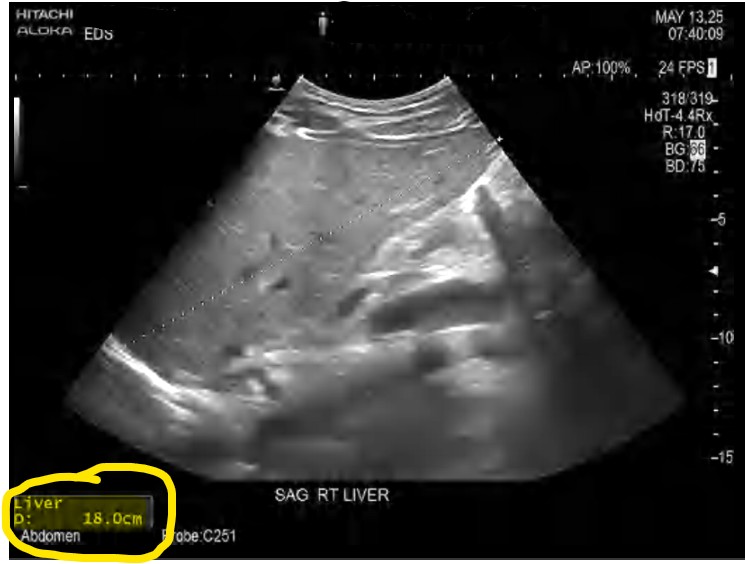

My Ultrasound Results:

Don’t let the word ‘mild’ fool you. In medical terms, ‘mild’ just means I don’t have cirrhosis yet. But looking at the data, my liver was 18c, significantly enlarged. Even though I had a normal BMI and ‘looked fine,’ my liver was inflamed and swollen. This was the wake-up call.